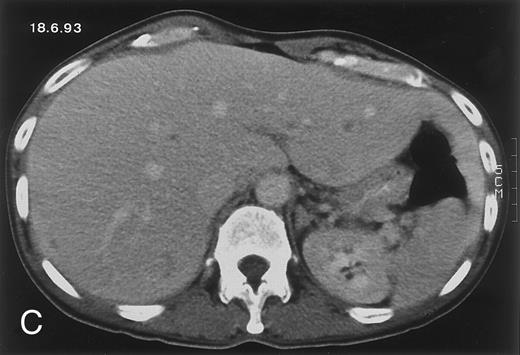

Radiologic evolution in patient A. (A) Postcontrast abdominal CT scan on March 16, 1993 shows multiple small hypodense areas in all segments of the liver, suggestive of hepatic candidiasis. Seven days previously, the patient had recovered from severe neutropenia after the first cycle of chemotherapy for AML. (B) On April 23, 6 days after the neutrophil count had dropped below 500/μL in the second cycle of chemotherapy, there is no evidence of focal lesions on postcontrast CT scan. (C) On June 18, when neutrophils were normalized for 46 days, CT scan again shows multiple small abscesses.

(D) On August 23, 15 days after the neutrophil count had dropped below 500/μL in the third chemotherapy cycle, focal liver lesions clearly decreased in size and number. (E) On September 30, 35 days after neutrophil recovery, multiple hepatic abscesses are seen (arrowhead). To show maximal extent of lesions the scan shown is at a slightly different level. (F) On June 16, 1994, 230 days after neutrophil recovery, the CT scan has normalized.